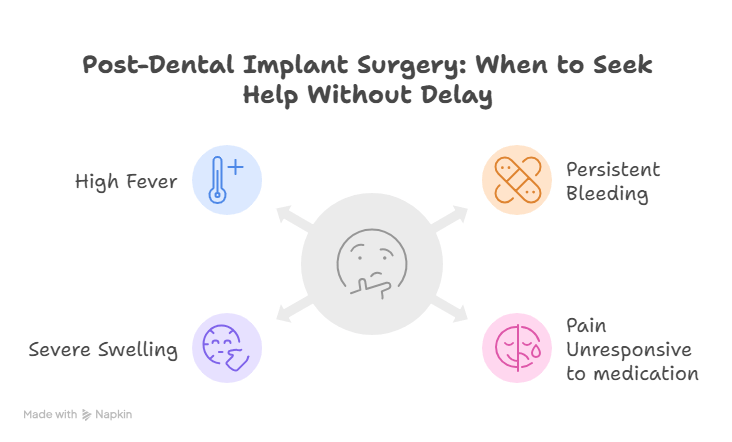

When to Seek Medical Help Immediately:

- Bleeding that persists after the first day

- Increasing pain or pain unresponsive to medication

- Severe swelling, pus, or foul odor in the mouth

- High fever